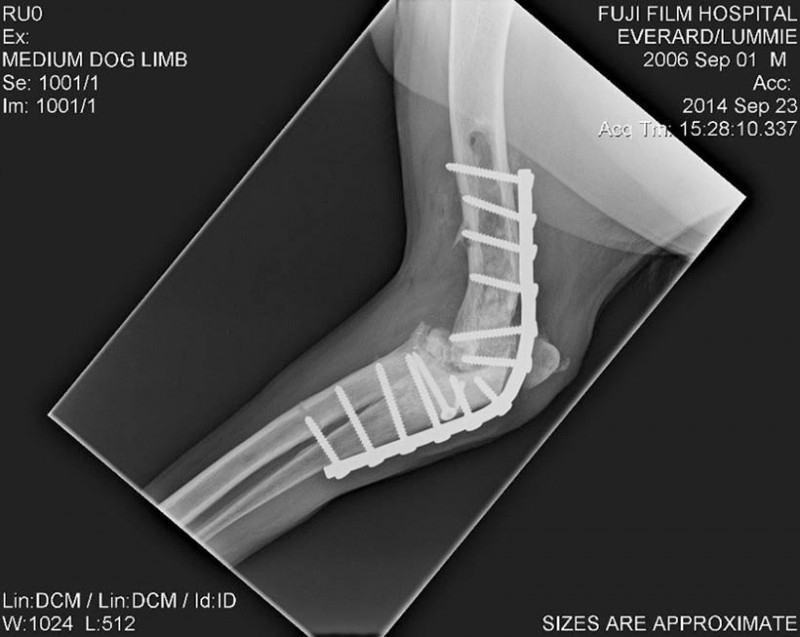

Figure 8. Postoperative image of an elbow arthrodesis.

Elbow arthrodesis is a salvage procedure for dogs with severe OA (Piermattei et al, 2006), but is typically reserved for cases where elbow replacement is not an option or has failed. Anecdotally, the procedure can result in relatively satisfactory function (Figure 8).